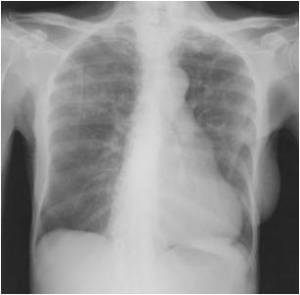

The following are examples of how Active TB may look on CXR:

A reading of “old scar” or “old granulomatous disease, not active” is WRONG unless there’s mention of a prior comparison film with “no change” or “stability”.